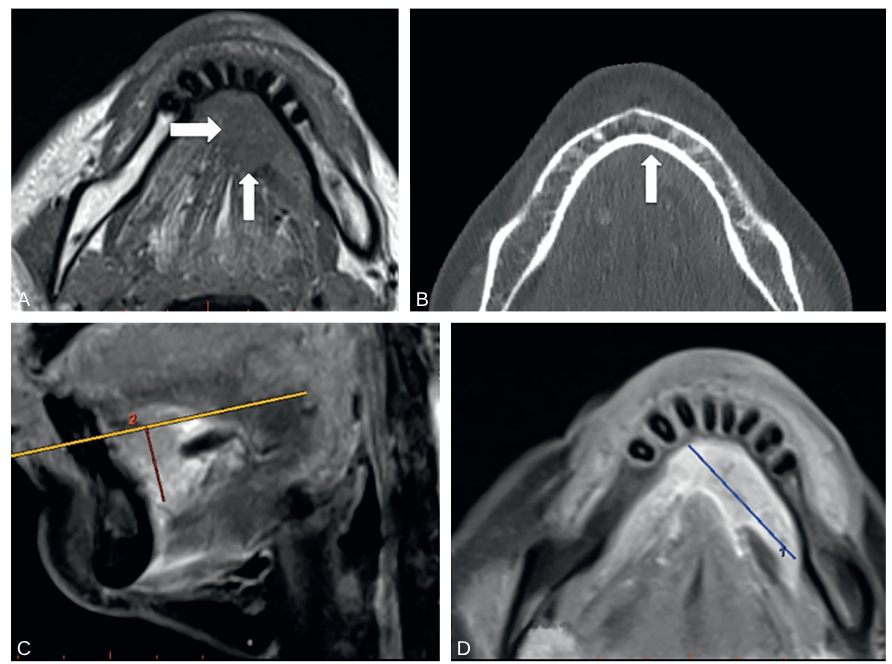

Fig. 72.1 IRM et TDM de la cavité orale : carcinome épidermoïde T3 du plancher.

Coupe transversale T1 (A) montrant un processus expansif en isosignal du plancher buccal antérieur (flèches), sans atteinte de l’os spongieux mandibulaire adjacent. TDM ne montrant pas d’érosion corticale (B, flèche) et confirmant l’absence d’atteinte osseuse. IRM en coupe sagittale T1 (C) avec saturation du signal de la graisse et injection de gadolinium, permettant de mesurer la profondeur d’infiltration. IRM en coupe transversale T1 (D) avec saturation du signal de la graisse et injection de gadolinium, permettant de mesurer le grand axe transversal.

Source : CERF, CNEBMN, 2022.